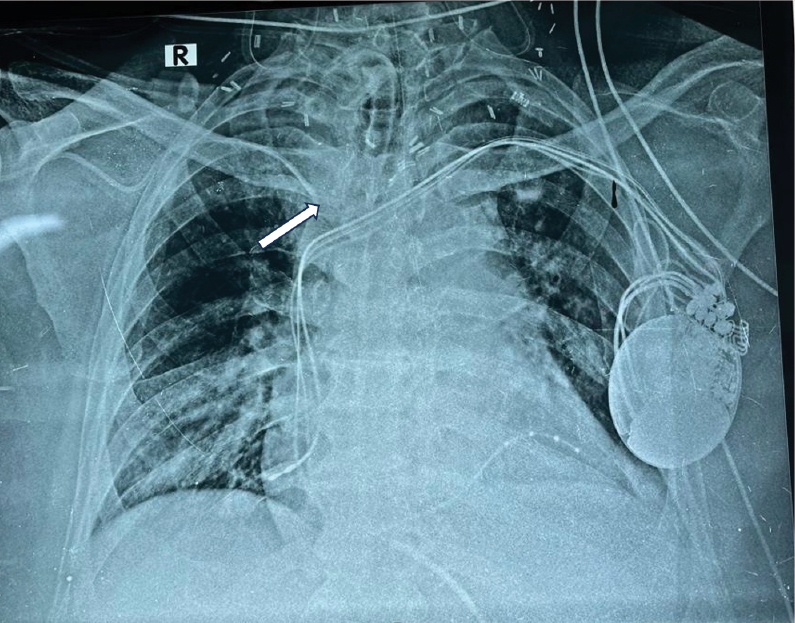

Prior to the surgery, central venous access was established by inserting a

right subclavian line by infraclavicular approach as per standard protocol1.

The subclavian venous access had been confirmed by a flash of blood and a

nonpulsatile drip of blood upon removing the needle, prior to inserting the

catheter. A check radiograph was done after the procedure which confirmed the

correct position of the line (Fig. 1).

Figure 1. Initial check radiograph showing appropriately

positioned subclavian venous catheter (white arrow).